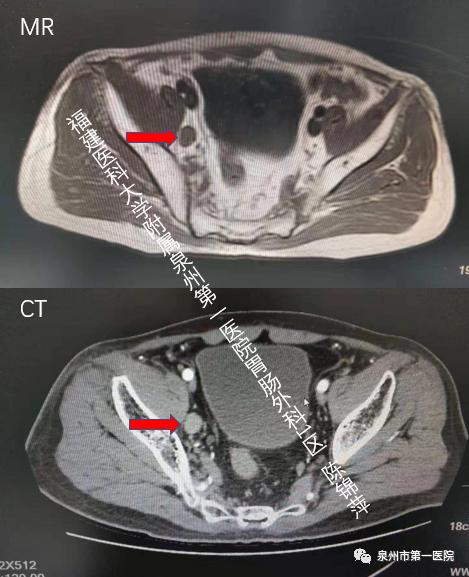

(影像资料显示肿瘤位置)

64岁的李阿婆,因“间断性便血2个月”来到泉州市第一医院胃肠外科1区就诊,科主任陈锦萍副主任医师接诊后,仔细询问患者病史,完善相关检查,结合影像资料,诊断为低位直肠癌,肿瘤下缘距离肛门4cm。